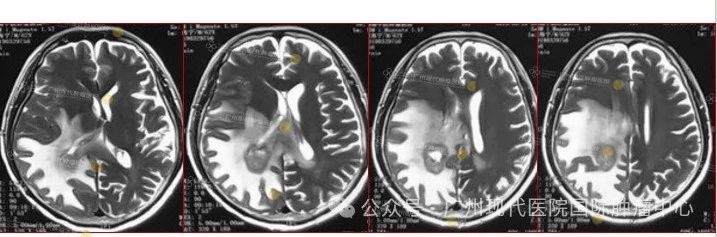

患者:63岁,男性

2013-11,体检发现肺部肿瘤,

2015-11,头颅MR检查提示颅内转移

2018-11,颅内肿瘤进展,无法接受后续治疗

2019-3,接受脑瘤粒子植入术

2019-7,颅内肿瘤基本消失,正常生活至今

2019年7月,颅内肿瘤已基本消失